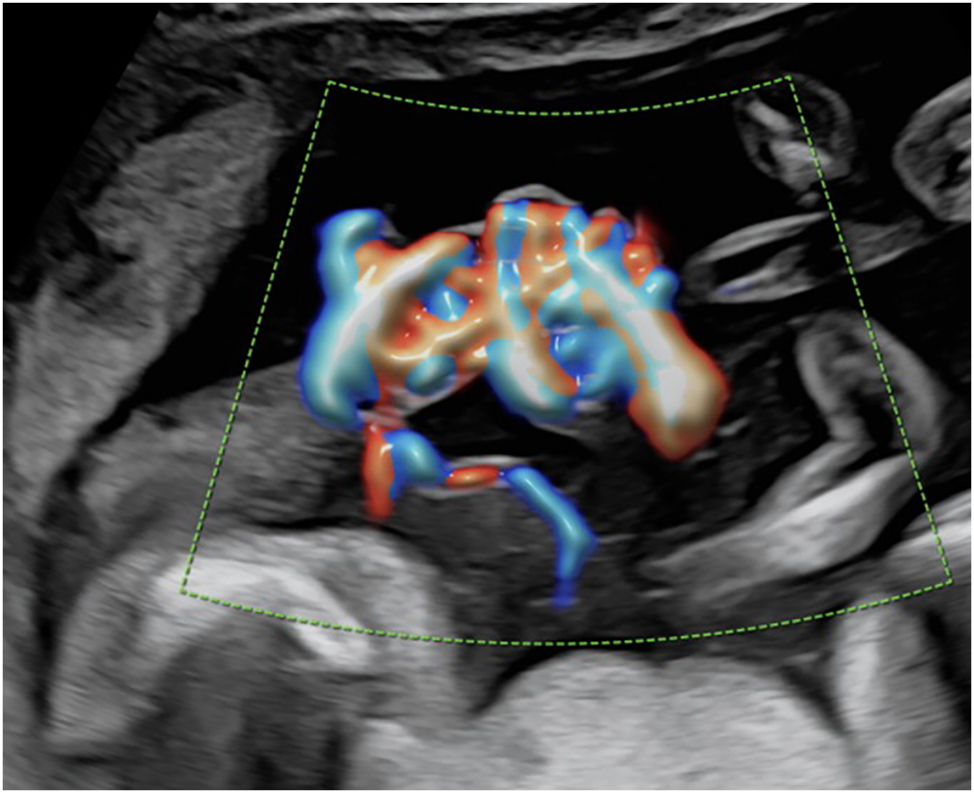

Around 5 % of monochorionic pregnancies are sharing a common amniotic sac and are therefore referred to as monoamniotic [12], 13]. These twins have an increased risk of fetal death and neonatal morbidity, which is mainly due to congenital anomalies, preterm birth, and complications from entanglement of the fetal umbilical cords. Indeed, discordant structural anomalies occur in up to 20 % of monoamniotic pregnancies making careful screening examinations mandatory [80], 81]. While almost all monoamniotic twin pregnancies are affected by umbilical cord entanglement (Figure 8), studies have demonstrated that the mere presence of cord entanglement as well as the presence of notching in the umbilical Doppler flow do not contribute to increased perinatal morbidity and mortality [82], [83], [84]. In monoamniotic pregnancies, TTTS occurs significantly less frequently and can be diagnosed through discordant bladder fillings and polyhydramnios in the shared amniotic sac.

Color Doppler image of typical umbilical cord entanglement in a monochorionic-monoamniotic twin pregnancy at 17 + 2 weeks of gestation.

Obstetric management of monoamniotic twin pregnancies includes prophylactic antenatal corticosteroids and continuous inpatient or intensive outpatient monitoring from approximately 26 to 28 weeks of gestation until planned cesarean section between 32 + 0 and 33 + 0 weeks of gestation [13], 85], 86].